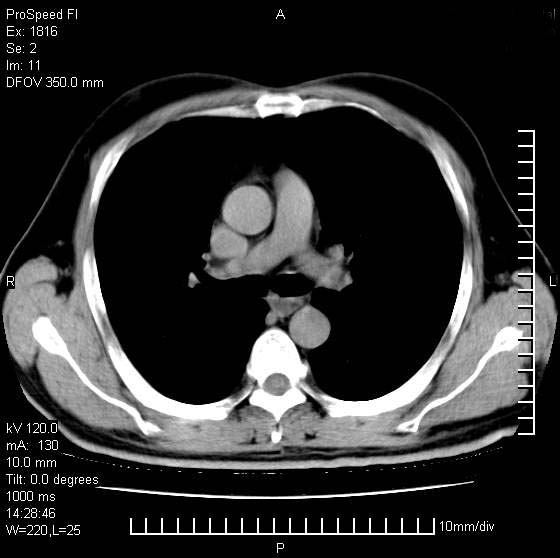

洞壁较厚内壁比较光整,两个病灶有关联性,纵隔淋巴结不大,考虑结核性空洞。

9年的结核应该呈现多形态病灶,该病例只能见到少许纤维索条影,似乎与结核的演变不太相符。空洞内壁不光整,外侧伴有胸膜粘连,考虑癌性空洞可能性大,期待结果。

壁较厚内壁比较光整,两个病灶有关联性,纵隔淋巴结不大,考虑结核性空洞